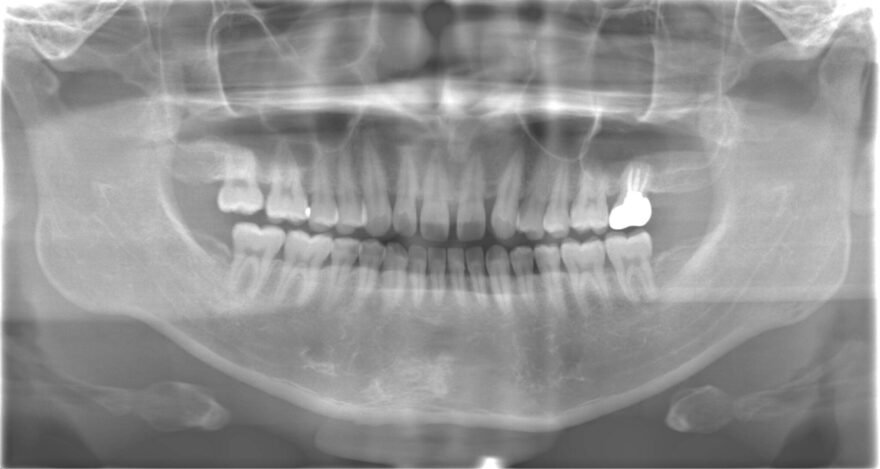

Before

困った時に、その場限りの治療でしのいできたものの、いよいよ顎まで痛くなってしまい、当院を受診されました。

7本のインプラント治療と18本のセラミック治療で、顎関節とのバランスまで考慮した機能的な噛み合わせを再建しました。

前歯インプラント2本→990,000円(税込)

《1本あたり495,000円(税込)》

奥歯インプラント5本→2,200,000円(税込)

《1本あたり440,000円(税込)》

前歯プレミアムセラミック10本→1,650,000円(税込)

《1本あたり165,000円(税込》

奥歯プレミアムセラミック8本→114,4000円(税込)

《1本あたり143,000円(税込)》

ファイバーコア6本→132,000円(税込)

《1本あたり22,000円(税込)》

前歯精密根管治療2本→220,000円

《1本あたり110,000円(税込)》

咬合再構成(全ての仮歯代とデジタルデザイン含む)25本→825,000円

《1本あたり33,000円(税込)》

総額 7,161,000円(税込)